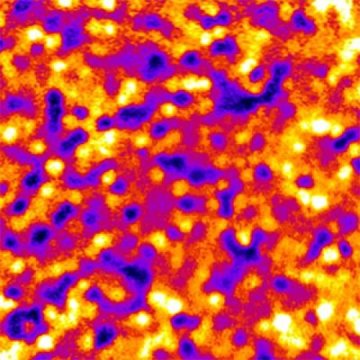

Cells of the retinal pigment epithelium (RPE) form unique patterns that can be used to track changes in this important layer of tissue in the back of the eye, researchers at the National Eye Institute (NEI) have found. Using a combination of adaptive optics imaging and a fluorescent dye, the researchers used the RPE patterns to track individual cells in healthy volunteers and people with retinal disease. The new finding could provide a way to study the progression and treatment of blinding diseases that affect the RPE. The study was published today in the journal JCI Insight. NEI is part of the National Institutes of Health (NIH).

“Studying cells of the retinal pigment epithelium in the clinic is like looking into a black box. RPE cells are difficult to see, and by the time signs of disease are detectable with conventional techniques, a lot of damage has often already occurred,” said Johnny Tam, Ph.D., the lead author of the study. “This study is proof-of-concept that we can use a fluorescent dye to reveal this unique fingerprint of the RPE, and to monitor the tissue over time.”

So, Tam turned to an FDA-approved fluorescent dye called indocyanine green (ICG) that is used to visualize the blood vessels in the back of the eye. While the dye fades from the blood vessels quickly, within about thirty minutes, the dye persists in the RPE for several hours, revealing a fluorescent mosaic pattern, with some cells appearing more brightly and others more dimly.

“Initially, we didn’t know how the dye was going to look,” said Tam. “We put the dye in and we got this pattern that at first looked kind of random. It was a big surprise that we could come back after a year, re-inject the dye, and see the same pattern.”

Tam and colleagues designed software that recognizes RPE patterns and then computes changes that occur from one imaging session to the next. For healthy volunteers, there was very little change in the RPE over several months, with the vast majority of the cells retaining a stable amount of ICG staining.

To find out whether this technique could detect the early stages of damage to the RPE, Tam and colleagues also imaged the eyes of people with conditions that can affect that part of the eye. First, Tam imaged the retinas of a patient with late-onset retinal degeneration (L-ORD), a condition that is thought to affect the RPE in later stages of the disease. The researchers found that the mosaic pattern of the RPE in a patient in the earlier stages of L-ORD was only slightly less stable than in healthy eyes, showing relatively minor changes in a few areas of the retina.

Second, the researchers imaged the eyes of a patient with Bietti crystalline dystrophy (BCD), a disease that causes progressive loss of RPE cells. Adaptive optics with ICG dye revealed not only that RPE cells in the patient with BCD were larger and less well organized than healthy cells at all time points, but also that there were drastic changes in the RPE mosaic pattern over time.